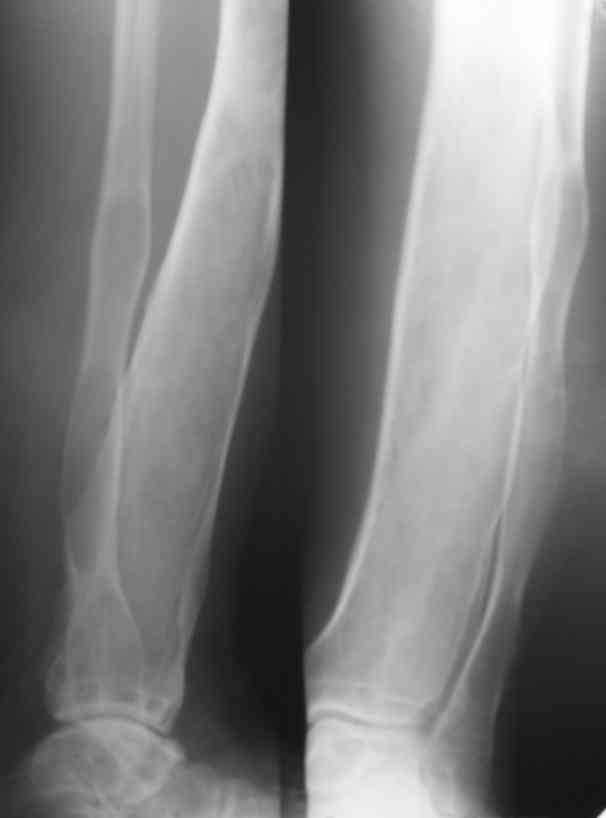

Я поддерживаю мнение доктора Odessky Jacob, что это образоавние возможно фиброзная дисплазия. Случай из моей практики - смотри рентгенснимки во вложении. Правда у моего пациента -полиосальная форма и болезнь проявилась в раннем детстве.